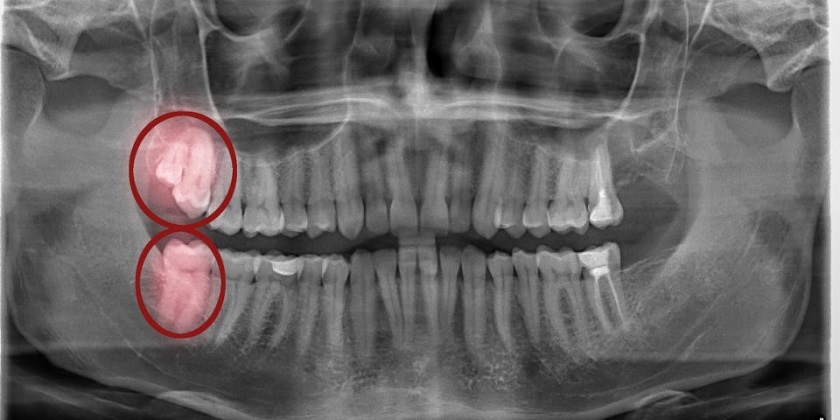

Để nhổ răng khôn, bạn cần trải qua một cuộc tiểu phẫu nhỏ. Không giống như những răng khác, răng số 8 – răng khôn khá phức tạp nên đòi hỏi bác sĩ thực hiện phải có chuyên môn tốt. Trường hợp răng khôn mọc ngầm có thể làm ảnh hưởng tới dây thần kinh, do đó việc định hướng răng mọc và đưa ra phương án nhổ hợp lý là điều cực kỳ quan trọng.

Nên loại bỏ cả 2 răng khôn ở cùng bên hàm trong một lần tiểu phẫu

Vậy nên để tránh phải dùng thuốc nhiều lần và tiết kiệm thời gian hơn bạn nên nhổ cả 2 răng khôn ở cùng phía trong một lần tiểu phẫu. Chi phí nhổ răng lúc này được tính dựa vào số răng cần nhổ, có thể thực hiện nhổ 2 răng khôn cùng lúc, thậm chí là cả 4 răng nếu sức khỏe của bạn cho phép.